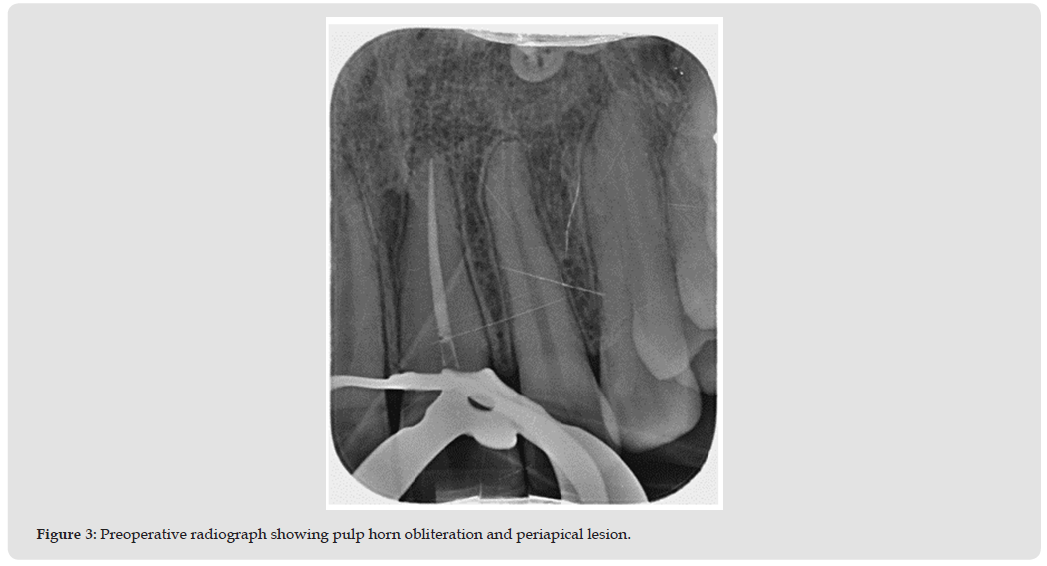

- Apical radiograph showed pulp horn obliteration and an incipient periapical lesion (Figures 1 & 2).

- Temporary closure with cotton pellet and Cavit™ (Figure 3).

- Temporary sealing with cotton pellet and Cavit™ (Figures 3-6).